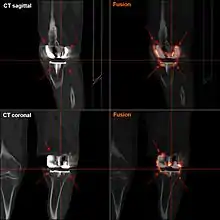

![]() |

Angles commonly measured before knee replacement surgery: |

To indicate knee replacement in case of osteoarthritis, its radiographic classification and severity of symptoms both should be substantial. Such radiography should consist of weightbearing X-rays of both knees: AP, lateral, and 30 degrees of flexion. AP and lateral views may not show joint space narrowing, but the 30-degree flexion view is most sensitive for narrowing. Full-length projections also are used in order to adjust the prosthesis to provide a neutral angle for the distal lower extremity. Two angles used for this purpose are:

- Hip-knee-shaft angle (HKS),[9] an angle formed between a line through the longitudinal axis of the femoral shaft and its mechanical axis, which is a line from the center of the femoral head to the intercondylar notch of the distal femur.[11]

- Hip-knee-ankle angle (HKA),[10] which is an angle between the femoral mechanical axis and the center of the ankle joint.[11] It is normally between 1.0° and 1.5° of varus in adults.[12]